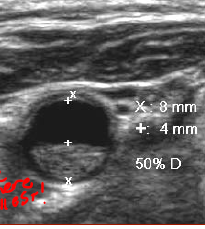

what is this?

what is the equation used in this type of imaging?

2D % stenosis measured in trans (measures diameter of plaque)

% stenosis = Vessel – Lumen / Vessel x 100

*secondary method to diagnose stenosis. used when we don’t see hemodynamic change which does not happen unless it is 50% stenosed. THIS EXAM IS DONE FO RMORE MILD rarely see this done clinically b/c most patients have >50% stenosis